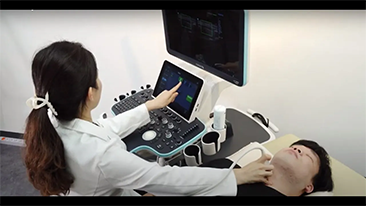

Selain kualitas gambar premium, Resona 7 juga meningkatkan kemampuan penelitian klinis dengan V Flow revolusioner untuk evaluasi hemodinamika vaskular, serta pengambilan penampang tercanggih dari rangkaian data 3D untuk diagnosis CNS pada janin. Kombinasi pengoperasian multisentuh berbasis gerakan yang paling intuitif dengan semua fitur klinis penting membuat Resona 7 menjadi gebrakan baru dalam inovasi ultrasound.